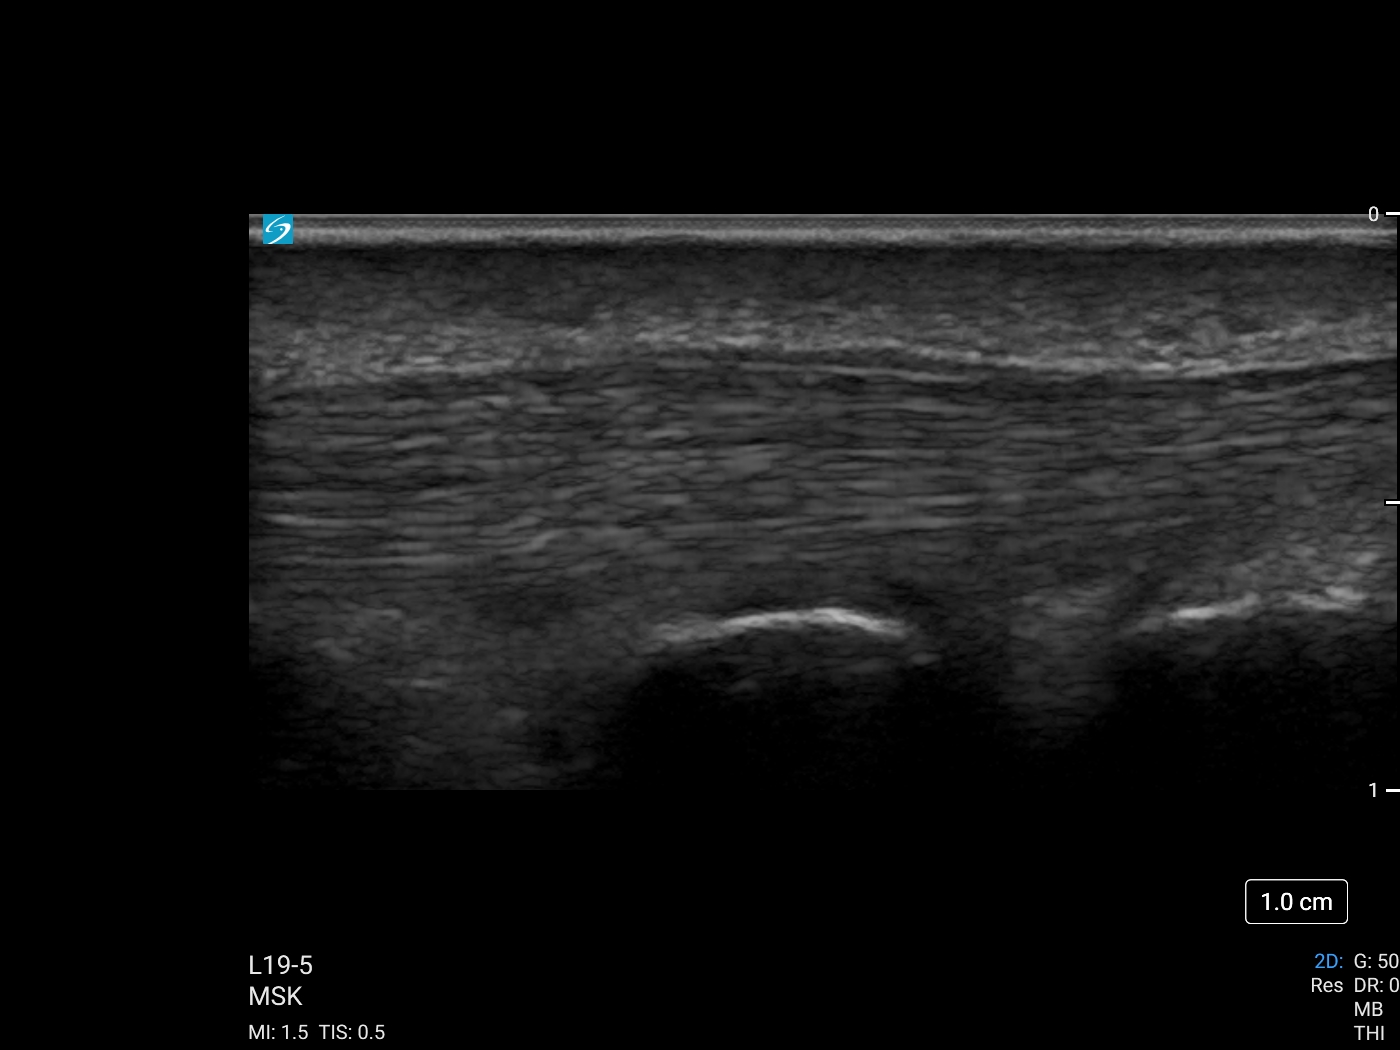

Thumb Flexor Tendon without UHF